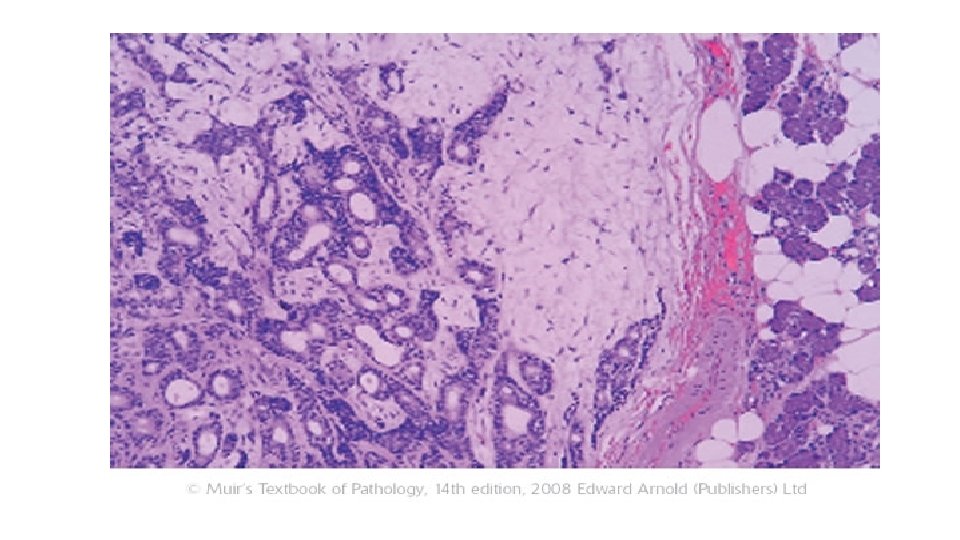

Local Invasion • Cancers grow by progressive infiltration, invasion, destruction, and penetration of the surrounding tissue. • They do not develop well-defined capsules. • The infiltrative mode of growth makes it necessary to remove a wide margin of surrounding normal tissue when surgical excision of a malignant tumor is attempted. • Surgical pathologists carefully examine the margins of resected tumors to ensure that they are devoid of cancer cells (clean margins). • Next to the development of metastases, local invasiveness is the most reliable feature that distinguishes malignant from benign tumors.